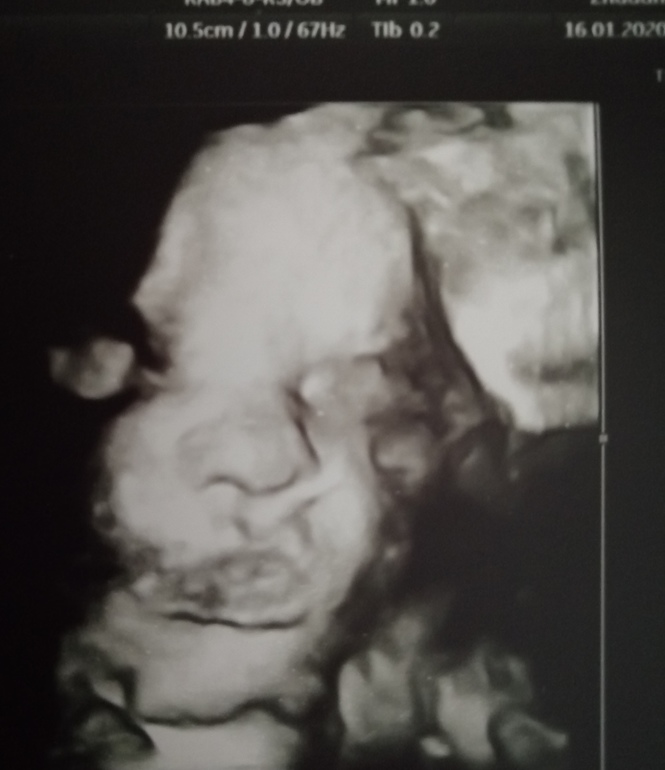

3й скрининг в 33

Вот и прошли мы последний скрининг 🙈 Это невероятно, каких-то полтора месяца до того как я смогу поцеловать "мой носик" как сказала узистка, пухлые щёчки, ладошки, попку, пяточки 🥰

По скринингу всё у нас замечательно, мы подрасли хорошо и весим 2050гр примерно. Врач сказала, что это на 32,3нед., а значит малышка будет не крупная. Да и не в кого у нас ей рождаться крупной)

Из двух обвитий и тазового в 27-30нед. сейчас осталось одно не тугое обвитие и теперь головное предлежание, головку прижала, но что-то мне кажется ещё покрутится, очень уж она любит кувырки. Плацента 2-3ст, кровотоки хороши, шейка 38, воды в норме, короче всё хорошо! И я счастлива 😘